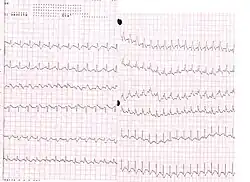

ECG

L'ECG n’est pas spécifique et les modifications sont très inconstantes. L'ECG d'un « cœur pulmonaire aigu », dont l'EP est l'étiologie principale, traduit une surcharge brutale du travail systolique du ventricule droit due à une augmentation souvent brutale de la postcharge du ventricule droit en rapport avec une occlusion artérielle pulmonaire[réf. nécessaire].

On peut retrouver certaines anomalies, de survenue précoce et réversibles. Cinq anomalies principales évoquent le diagnostic de cœur pulmonaire aigu[10] :

- apparition d'une fibrillation auriculaire rapide. Tachycardie sinusale, retrouvée dans environ 25 % des EP ;

- aspect S1Q3, retrouvé dans environ 50 % des cas et non spécifique. Défini par une grande onde S en DI et une grande onde Q en DIII ;

- bloc de branche droit incomplet, fréquent mais fugace. Défini par une durée du QRS > 0.08 s et < 0.12 s et par un retard à l'inscription de la déflexion intrinsécoïde en V1 > 0.04 s. Les QRS ont un aspect RSR' en V1 ;

- déplacement vers la gauche de la zone de transition des QRS, retrouvée dans environ 50 % des cas ;

- troubles de repolarisation, retrouvé dans environ 70 % des cas et persistant plusieurs jours, avec inversion des ondes T dans le territoire antérieur (V1 à V3) avec des ondes T pointues et symétriques, évocatrices d'ischémie.

- Signes électrocardiographiques évocateurs d'un cœur droit aigu[10]

- Fibrillation auriculaire rapide.

- Aspect S1Q3

- Bloc de branche droit incomplet

- Déplacement vers la gauche de la zone de transition

- Inversion des ondes T en antérieur